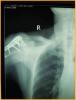

患者女,72岁,诊断为:肱骨近端骨折。

行肱骨近端锁定型钉板(PHILOS)固定术,手术过程:采用全麻或斜方肌阻滞麻醉,用沙滩椅体位,术中肱骨头复位后,用二至三枚克氏针临时固定保持复位,并使其余骨折块复位,然后透视确认复位质量。用5号不可吸收缝线将大小结节缝合修复,再选用适当长度的锁定钉板置于肱骨近端和肱骨干的外侧面。注意避免将钢板放置的过高以致成角螺钉的位置不合适而不能达到最佳骨接触。可用一枚非锁定螺钉固定于肱骨干上可使钢板远近端滑动调整位置。然后使用导向器上锁定螺钉使钢板和螺钉一体化。固定完成后再次透视确认无误,处理好软组织后逐层关闭切口。